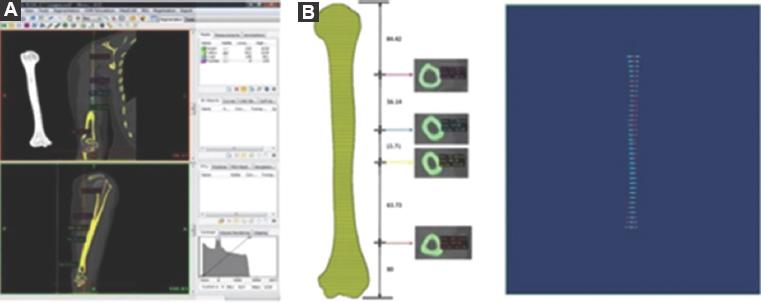

Se obtuvieron imágenes en formato DICOM (Digital Imaging and Communication in Medicine) a partir de un estudio tomográfico y se procesaron con el software Mimics Innovation Suite (Materialise Inc. Leuven, Bélgica), versión 17.

Por medio del software se realizó la medición de los húmeros para su clasificación (chico, mediano, grande) y el conocimiento de las dimensiones (longitud y diámetro). Además, se realizó la limpieza del canal medular de las TC para una medición más exacta del diámetro de los cortes tomográficos.

Los parámetros de medición de la TC se obtuvieron a partir de 8 cm de la zona distal y 6 cm de la zona proximal, cada 10 cortes a partir de estas. Se diseñaron polilíneas y se crearon curvas (Fig. 3 A y B).

Figura 3 A: cortes tomográficos realizados con el software. B: creación de polilíneas como guía para la limpieza y la medición de las tomografías. Software: Mimics, 3-matic (Materialise Inc., Leuven Bélgica).

Los cortes tomográficos obtenidos se trabajaron en 3-matic (Materialise Inc., Leuven Bélgica) para la medición del diámetro y la recopilación de los datos. De las imágenes obtenidas por el software, se realizaron tres mediciones del canal medular: interna (diámetros de los vástagos), interna (diámetros de la corona) y externa (diámetro del implante), además de la longitud del húmero (Fig. 4).

Figura 4 Medición de los cortes tomográficos del húmero (longitud y diámetro), limpieza del canal medular de tomografías computadas para su medición (8 cm distal y 6 cm proximal). Creación de polilíneas, curvas y medición. Software: Mimics, 3-matic (Materialise Inc., Leuven Bélgica).